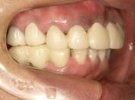

47歳女性

ブリッジや義歯でも可能な症例ですが、残っている歯を守りたいという患者さんの希望によりインプラント施術。

なお、この患者さんは歯医者の方で、専門知識の高い歯科医師の方にも喜んでもらえて大変光栄でした

術前

↓↓↓↓

術後